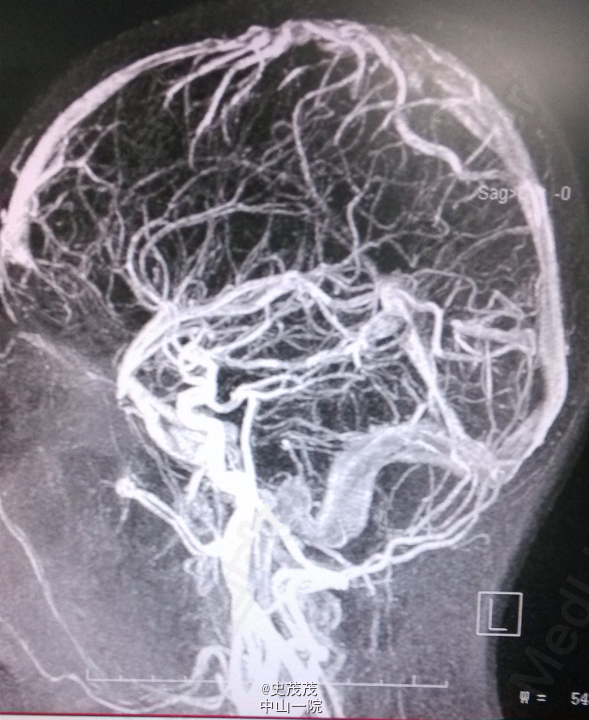

入院查体:神清,对答切题,记忆力及智力粗测正常,双侧瞳孔等大等圆,直径约2.5mm,对光反射灵敏,伸舌居中,耳鼻无异常分泌物,颈软,无抵抗,Kernig Sign(-),粗侧左眼视野变窄,其余颅神经检查未见明显异常,四肢活动好,肌力Ⅴ级,肌张力正常,生理反射存在,病理反射未引出。 辅助检查:CT:左侧枕顶叶片状高密度影伴周围低密度影,病灶范围约2.3cm×3.5cm×34cm,内见钙化灶。颅内动脉VR、MIP重建显示:左侧枕顶叶可见团状异常血管影,部分血管壁可见钙化斑,有左侧大脑中动脉供血。考虑左侧枕顶叶血管畸形并出血,建议复查。头颅DSA提示未看到输出静脉,需鉴别动静脉畸形及肿瘤。 头部MR增强扫描+头部血管扫描:左侧枕顶叶团块状异常信号影,大小约3.6×2.4×3.4cm,T1WI呈高低混杂信号,T2WI呈高信号,周围可见大片水肿区,增强后病变边缘有小片状强化影,肿块内见粗大血管影,肿块血管与邻近大脑中动脉、大脑中浅静脉关系密切。诊断提示左侧枕顶叶病变,考虑肿瘤与血管畸形鉴别,前者可能性大,合并出血,建议进一步检查